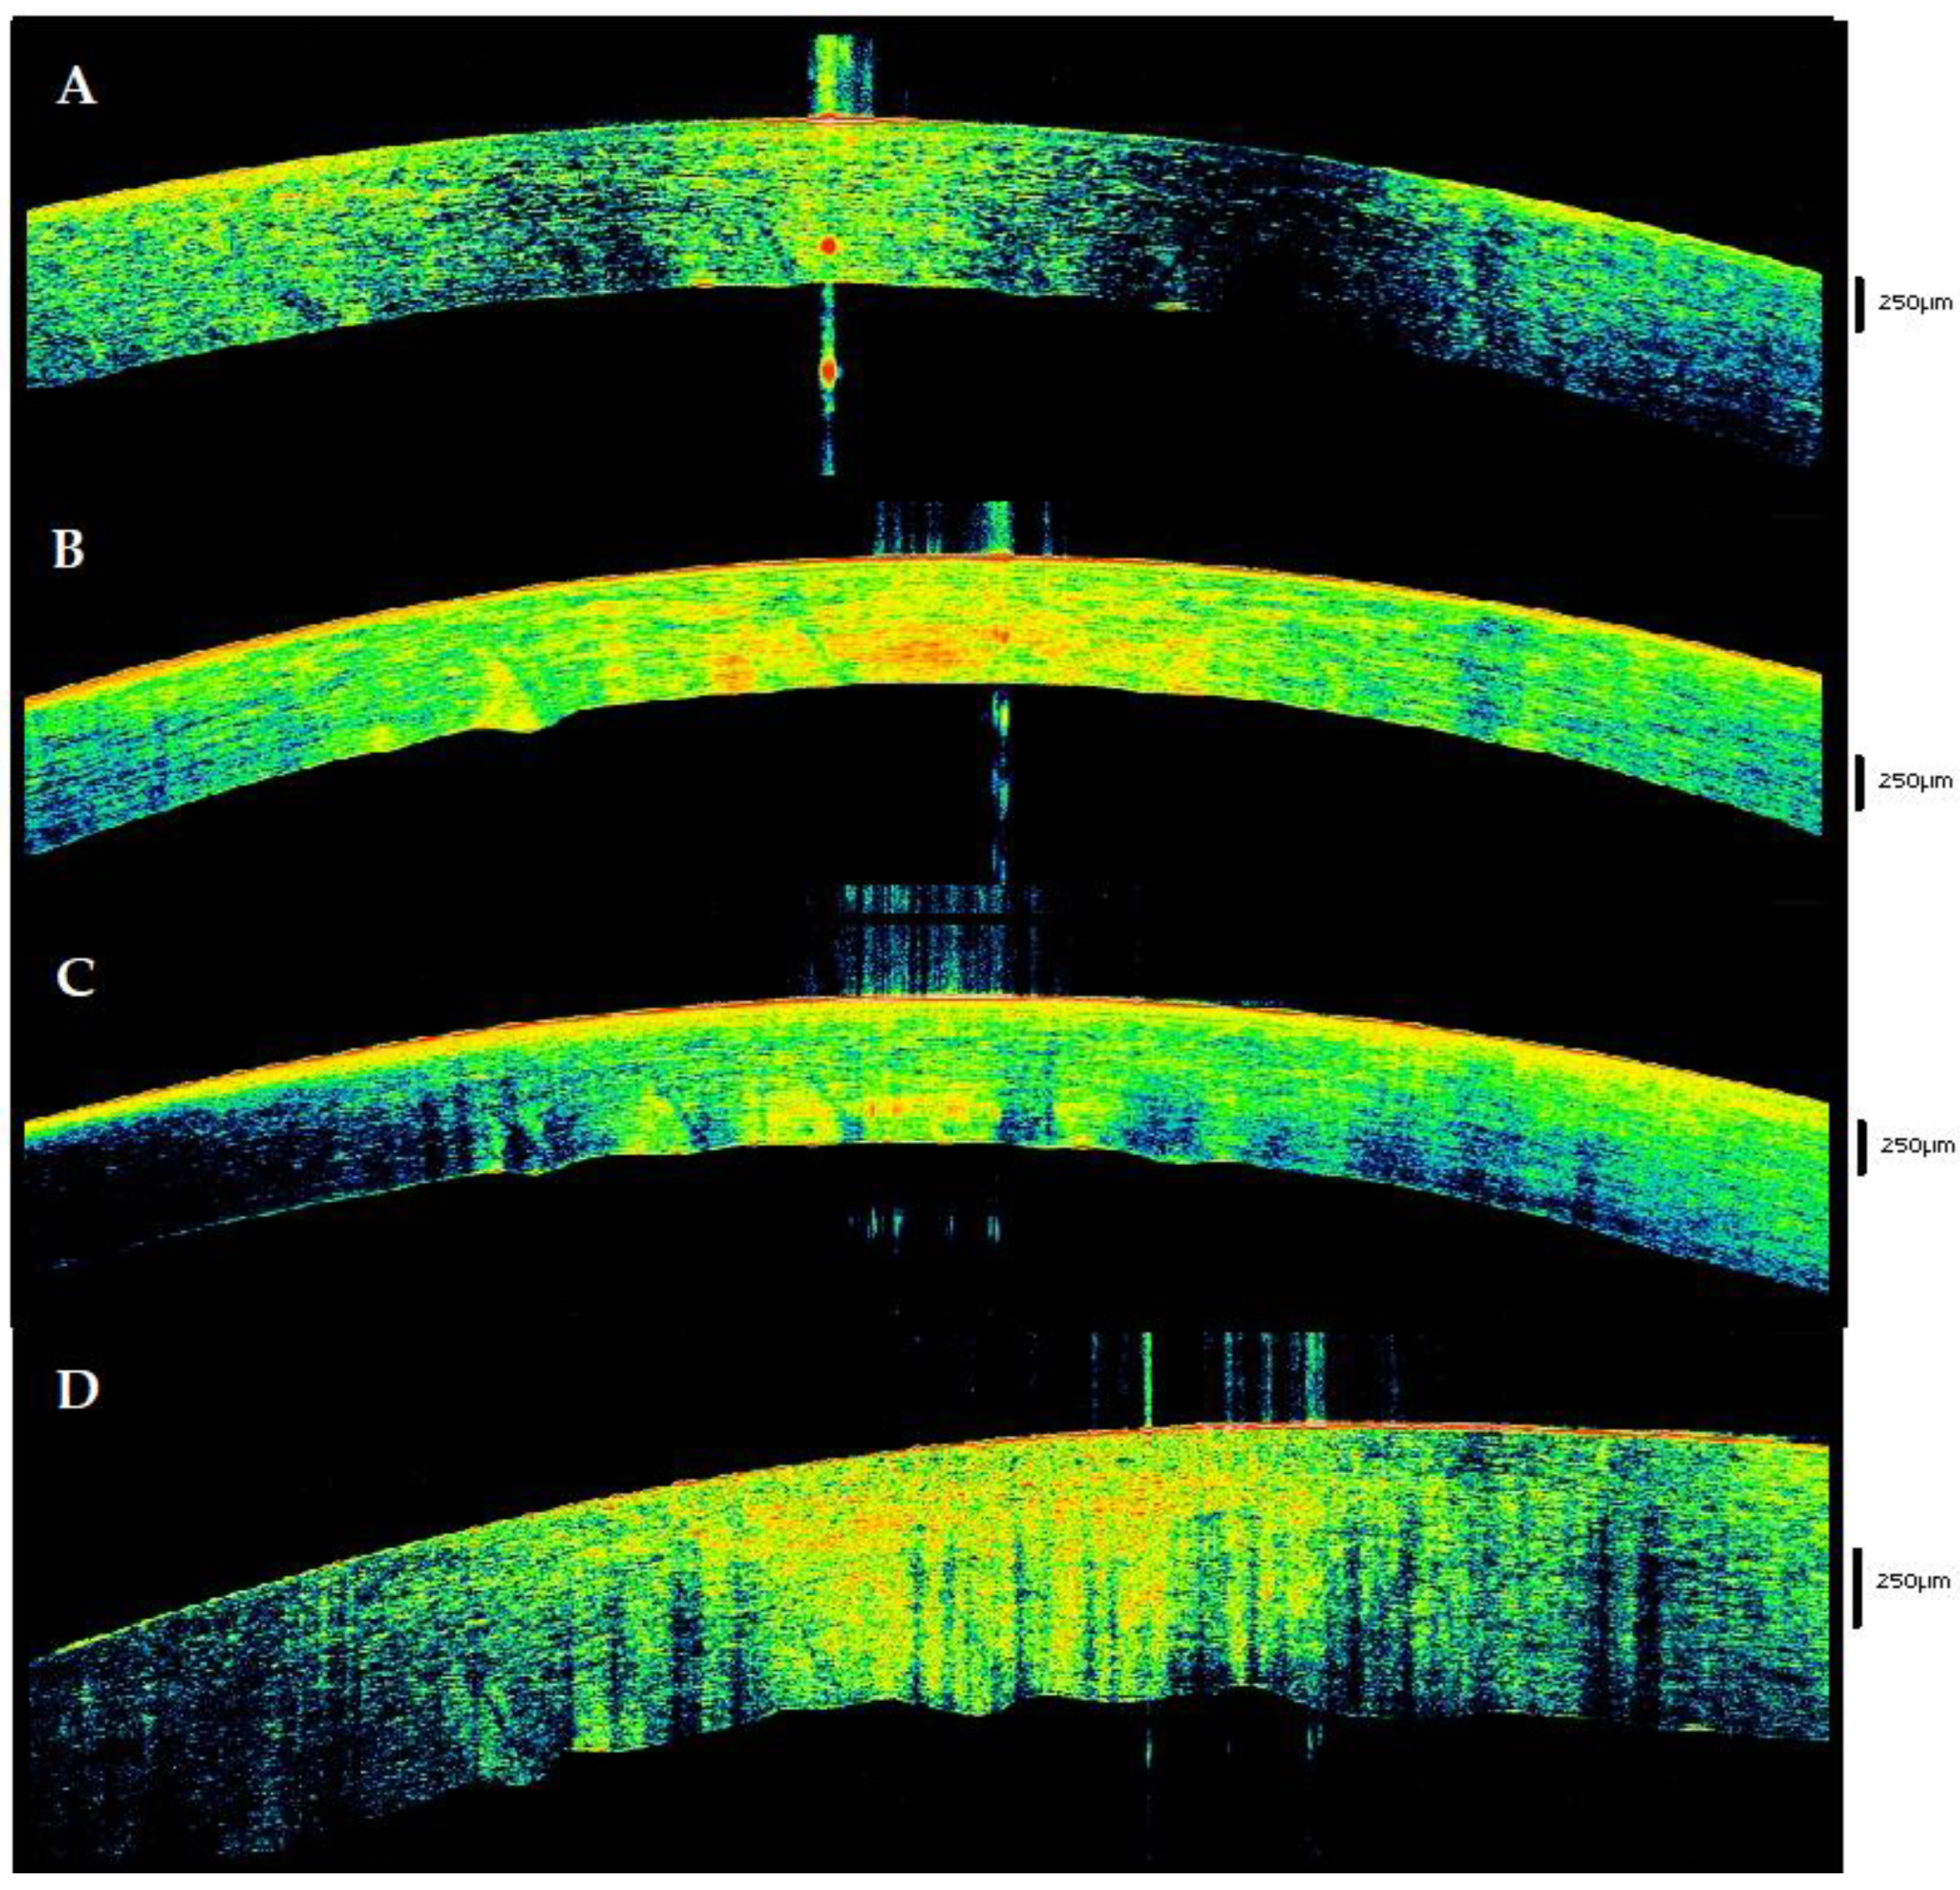

| 3–6 | Lacrimal tear progressively disappears. Hyperreflectivity with a “binary” pattern. | Initial thinning with differentiation between the anterior (hyper-reflective) and posterior (hypo-reflective) parts. | Hyper-reflective whit spots. | Initial sawtooth and stromal striae are detectable in the stroma. |

| 6–9 | Single, hyperreflective layer. | Decrease in stromal thickness. Hyperreflectivity in ¾ of anterior tissue in 68.5% of cases. | Unchanged. | Unchanged |

| 9–12 | Unchanged | Hyperreflectivity reaches the endothelium and takes a trapezoid form. | Enhancing of hyperreflectivity. | Stromal striae (65.8%) Sawtooth sign (78,2%) Initial loosing of the spheric form of the tissue in 21.7% of cases |

| 12–17 | Unchanged | Rising of posterior stroma hypo-reflectivity that in some cases reaches the middle of the tissue. | Are evident areas of hypo-reflectivity. | Stromal striae (100%) Sawtooth sign (100%) Initial loosing of the spheric form of the tissue in 34.7% of cases |